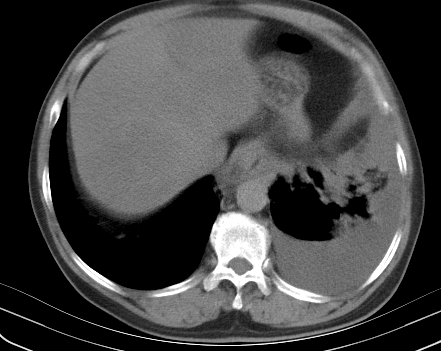

以下是引用老爱克斯新网客在2008-7-31 6:30:00的发言:[br]左肺上叶大片状病灶,左肺上叶支气管狭窄呈鼠尾状,左肺门增大,纵隔内见肿大淋巴结,左侧胸腔积液,余肺清晰。左肺中心型肺癌淋巴结转移,

以下是引用zjzjr在2008-7-31 8:45:00的发言:[br]考虑左侧中心性肺癌伴阻塞性肺炎,左肺上叶肺不张,纵隔淋巴结转移;左侧胸腔积液。建议行纤支镜检查。

以下是引用zjb在2008-7-31 6:32:00的发言:[br]左侧中心性肺癌 阻塞性肺炎 肺不张 胸腔积液 建议气管镜

以下是引用sdzyy在2008-7-31 8:47:00的发言:[br]病灶较治疗前有所进展,胸水增多, 左侧中心性肺癌 并 阻塞性肺炎 肺不张 胸腔积液 可能性大; 建议气管镜检查。 [br] [br]